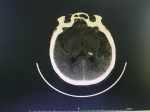

丘腦出血找準(zhǔn)病因,積極處理可有效減輕病情 關(guān)鍵疾?。?a href="http://m.akellydesign.com/tags/so/丘腦出血-4-1.html" target="_blank">丘腦出血冠狀動(dòng)脈粥樣硬化性心臟病 現(xiàn)病史【一般資料】 女性,77歲,農(nóng)民 【主訴】 頭暈1周,加重伴惡心3天。 【現(xiàn)病史】患者于1周前無(wú)明顯誘因出現(xiàn)頭暈,未引起重視。3天前頭暈加重,伴惡心,下頜部不自主抖動(dòng),行走不穩(wěn),故入院。入院時(shí)可直立位行走,自覺(jué)輕微眩暈、惡心,活動(dòng)后視物旋轉(zhuǎn)。本次發(fā)病以來(lái)無(wú)頭痛、發(fā)熱,無(wú)咳嗽、咳痰、氣喘,無(wú)腹痛、腹瀉。來(lái)時(shí),患者精神食欲差,大小便正常。 【既往史】平素身體健康,否認(rèn)肝炎、結(jié)核等傳染病史,患高血壓8年,血壓最高180/100mmHg,平素服“吲達(dá)帕胺 2.5mg 1天1片”。膝關(guān)節(jié)疼痛30年,左...